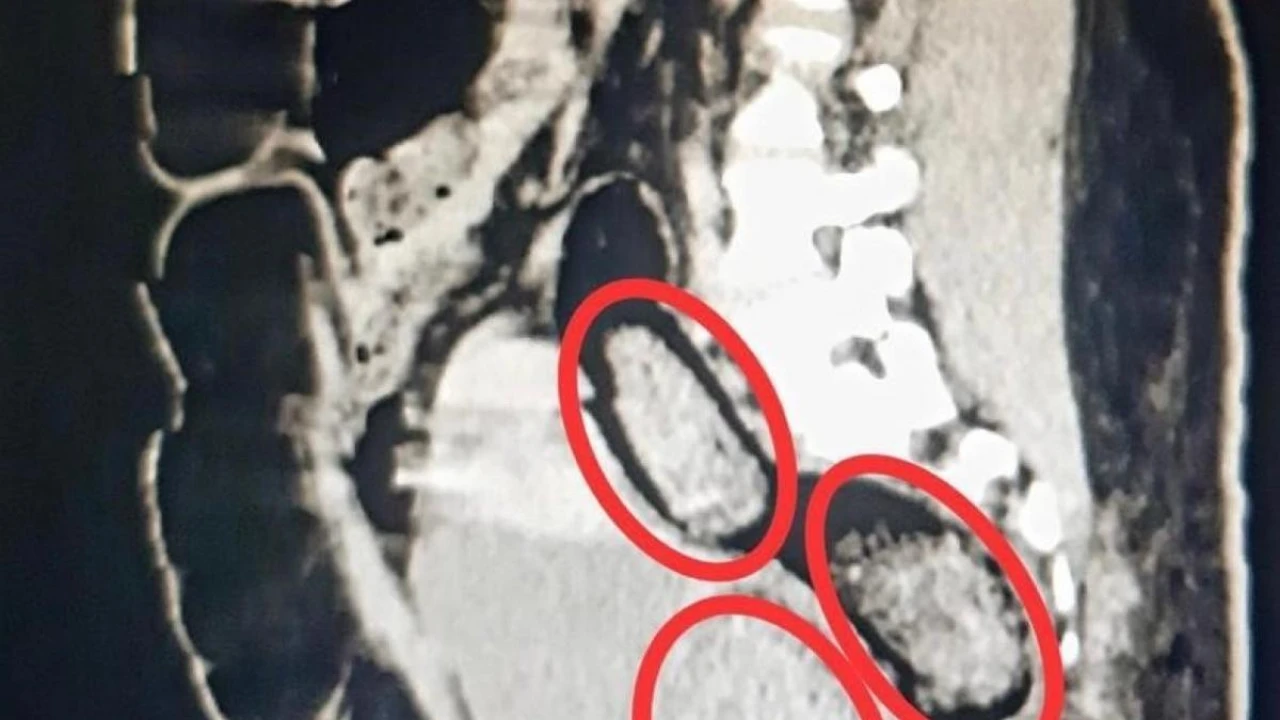

Otobüste gözaltına alınan Hadıs Aeınezad’in yapılan iç beden muayenesinde bağırsaklarında cisim olduğu tespit edildi. Hadıs Aeınezad’ın makadına saklanmış bir şekilde 3 parça 318 gram metamfetamin uyuşturucu maddesi cerrahi müdahaleyle çıkarıldı.